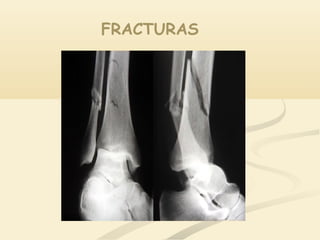

FRACTURAS

Definición

Es una lesión producida por un golpe que vence la

elasticidad y resistencia del hueso

Clasificación

Cerradas o Simples

Abiertas o Expuestas